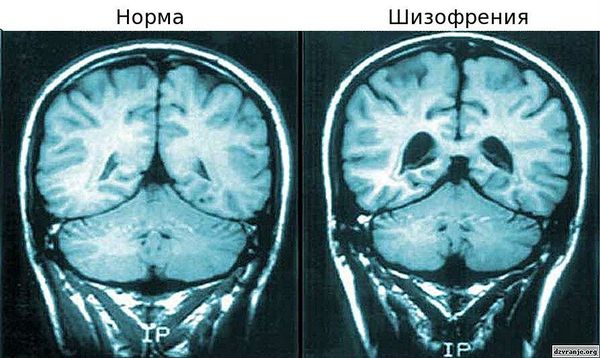

>>943049

Это пиздёж, это не шизофрения а какая-нибудь деменция. От шизофрении не образуются полости в мозге.